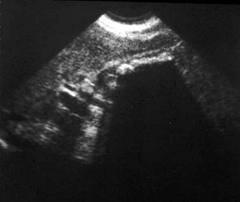

COLELITIASIS